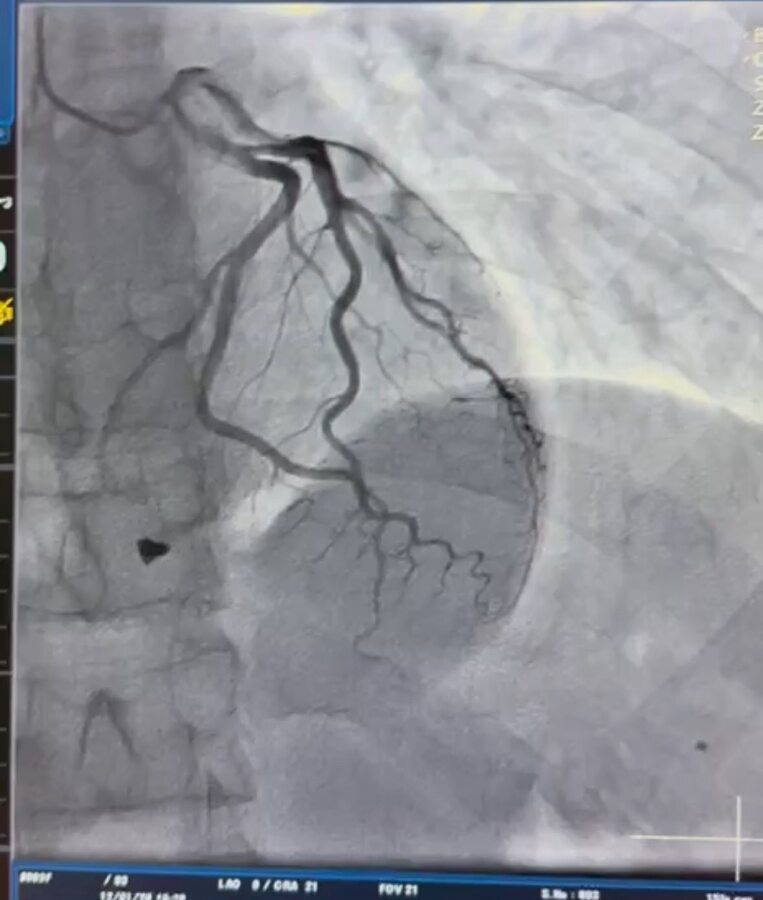

Під час детального обстеження медики встановили, що металевий уламок після поранення знаходився в зоні клапанного апарату серця та пошкодив папілярний м’яз тристулкового клапана. Це створювало ризик втрати повноцінної роботи клапана і могло призвести до важких ускладнень.

Після ретельного аналізу характеру травми кардіохірургічна команда лікарні ухвалила рішення про оперативне втручання. Під час операції лікарі видалили вогнепальний осколок та виконали пластику тристулкового клапана, що дозволило відновити його функцію і стабільну роботу серця.